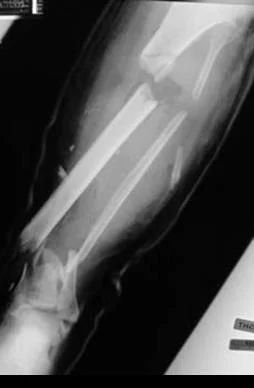

Low Energy vs. High Energy

| Low Energy | High Energy |

![]() | ![]() |